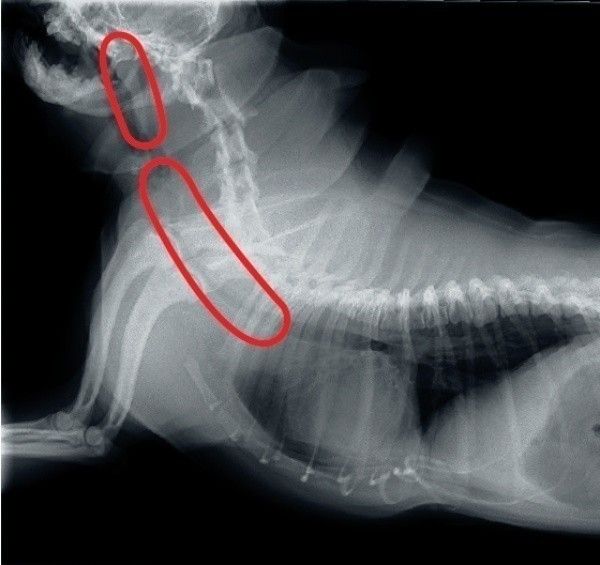

呼吸器の病気は、飼い主さんのチェックだけでは気づきにくいことがあり、動物病院でのレントゲン検査が必要になることも。シニア犬は半年に1回のペースで行うと安心です。

気管虚脱の場合は、セキ止めや気管支を拡張する薬を使いながら、長く付き合っていくケースが一般的です。そのほか、気管がつぶれないようにする高度な外科手術で治療することもあります。